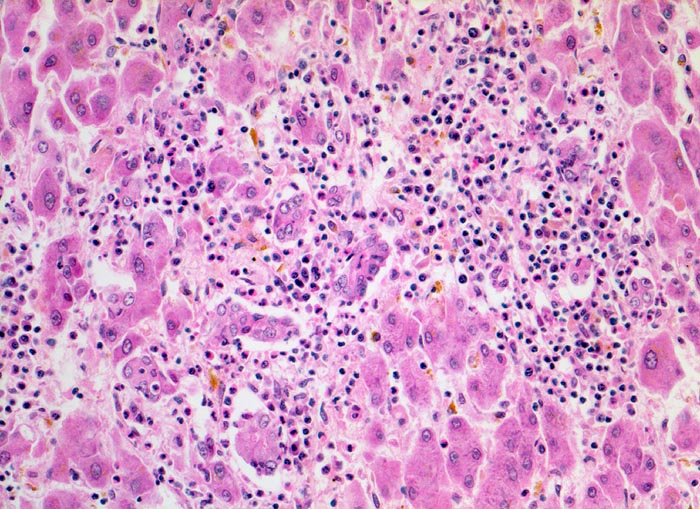

Das histologische Bild der akuten Hepatitis vom Virustyp ist gekennzeichnet durch eine lobuläre Entzündung bei fehlender portaler Fibrose und nur geringer entzündlicher Infiltration der Portalfelder. Es finden sich ballonierte Hepatozyten, Apoptosen ( 1164) und fleckige Nekrosen. Perivenuläre Nekrosen, Brückennekrosen oder konfluierende multilobuläre Nekrosen und eine läppchenzentrale Cholestase können vor allem in klinisch fulminant verlaufenden Fällen nachgewiesen werden. Zahlreiche Makrophagen, welche Diastase-PAS positives Zeroidpigment ( 4319) von phagozytierten nekrotischen Hepatozyten enthalten, zeugen im subakuten Stadium von einer abgelaufenen akuten Hepatitis mit Parenchymnekrosen. Eine Unterscheidung der verschiedenen Typen der viralen Hepatitis und einiger Formen medikamentöser Hepatitiden gelingt rein morphologisch aufgrund des unspezifischen Bildes meist nicht. Für eine ätiologische Klassifizierung sind zusätzliche klinische Angaben erforderlich (Anamnese, Medikamente, Serologie).